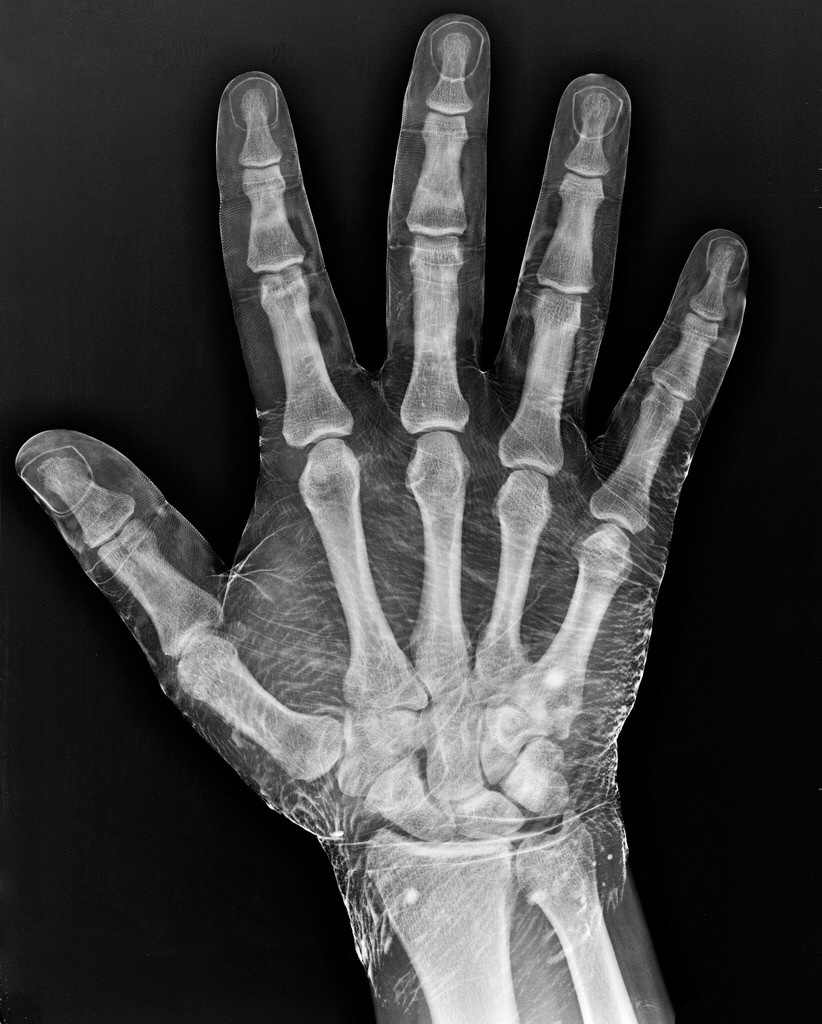

בתמונה שצירפתי אפשר לראות דרך כמה מפרקים עובר הלחץ מהיד עד שהוא מגיע לקצה האגודל וככול שאתם לוחצים יותר חזק וליותר זמן האגודל נשחק יותר